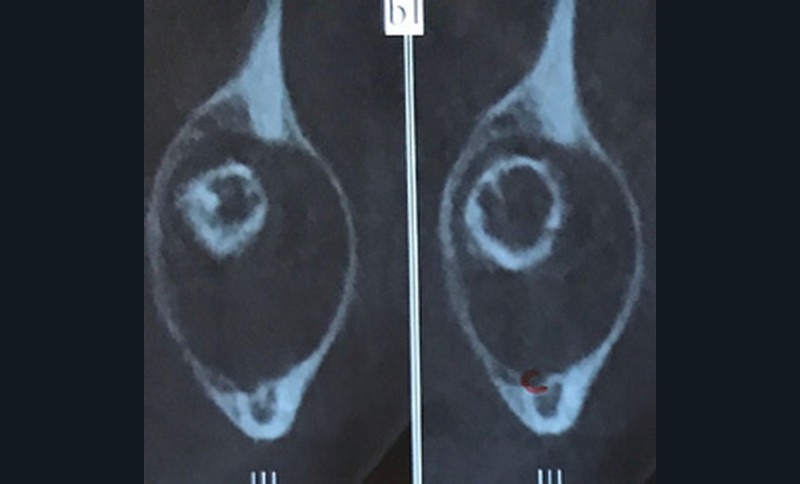

La radiographie panoramique permet une première interprétation de la lésion osseuse (localisation, nombre, taille approximative, etc.). Cet examen est souvent complété par un bilan d’imagerie en trois dimensions de type Cone Beam [4]. Il précisera le volume et les limites de la lésion ainsi que ses rapports avec les structures anatomiques avoisinantes (tableau 1). Ces données radiologiques confrontées à l’examen clinique et à la fréquence relative des lésions permettent de réaliser un diagnostic d’intuition qui orientera la prise en charge.